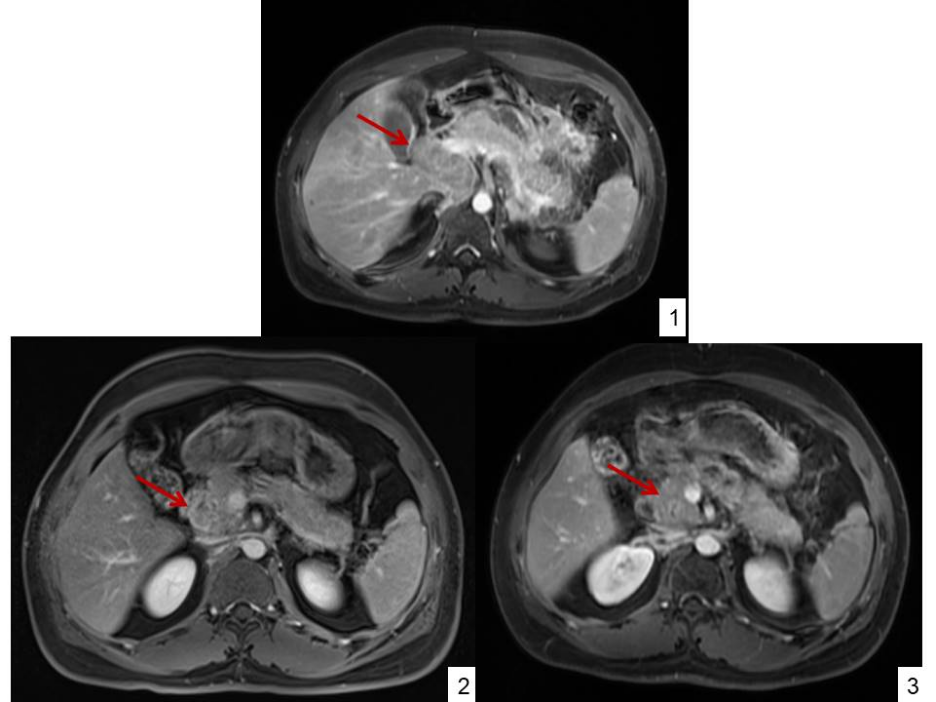

附图3:1)2021-12-16 治疗前:可见腹腔及腹膜后多发淋巴结转移,部分融合成片,直径约60mm×29mm。2)2022-2-25 2个疗程后:腹腔及腹膜后淋巴结较前缩小,直径约39mm×23mm。3)2022-4-12 4个疗程后:腹腔及腹膜后淋巴结较前缩小。